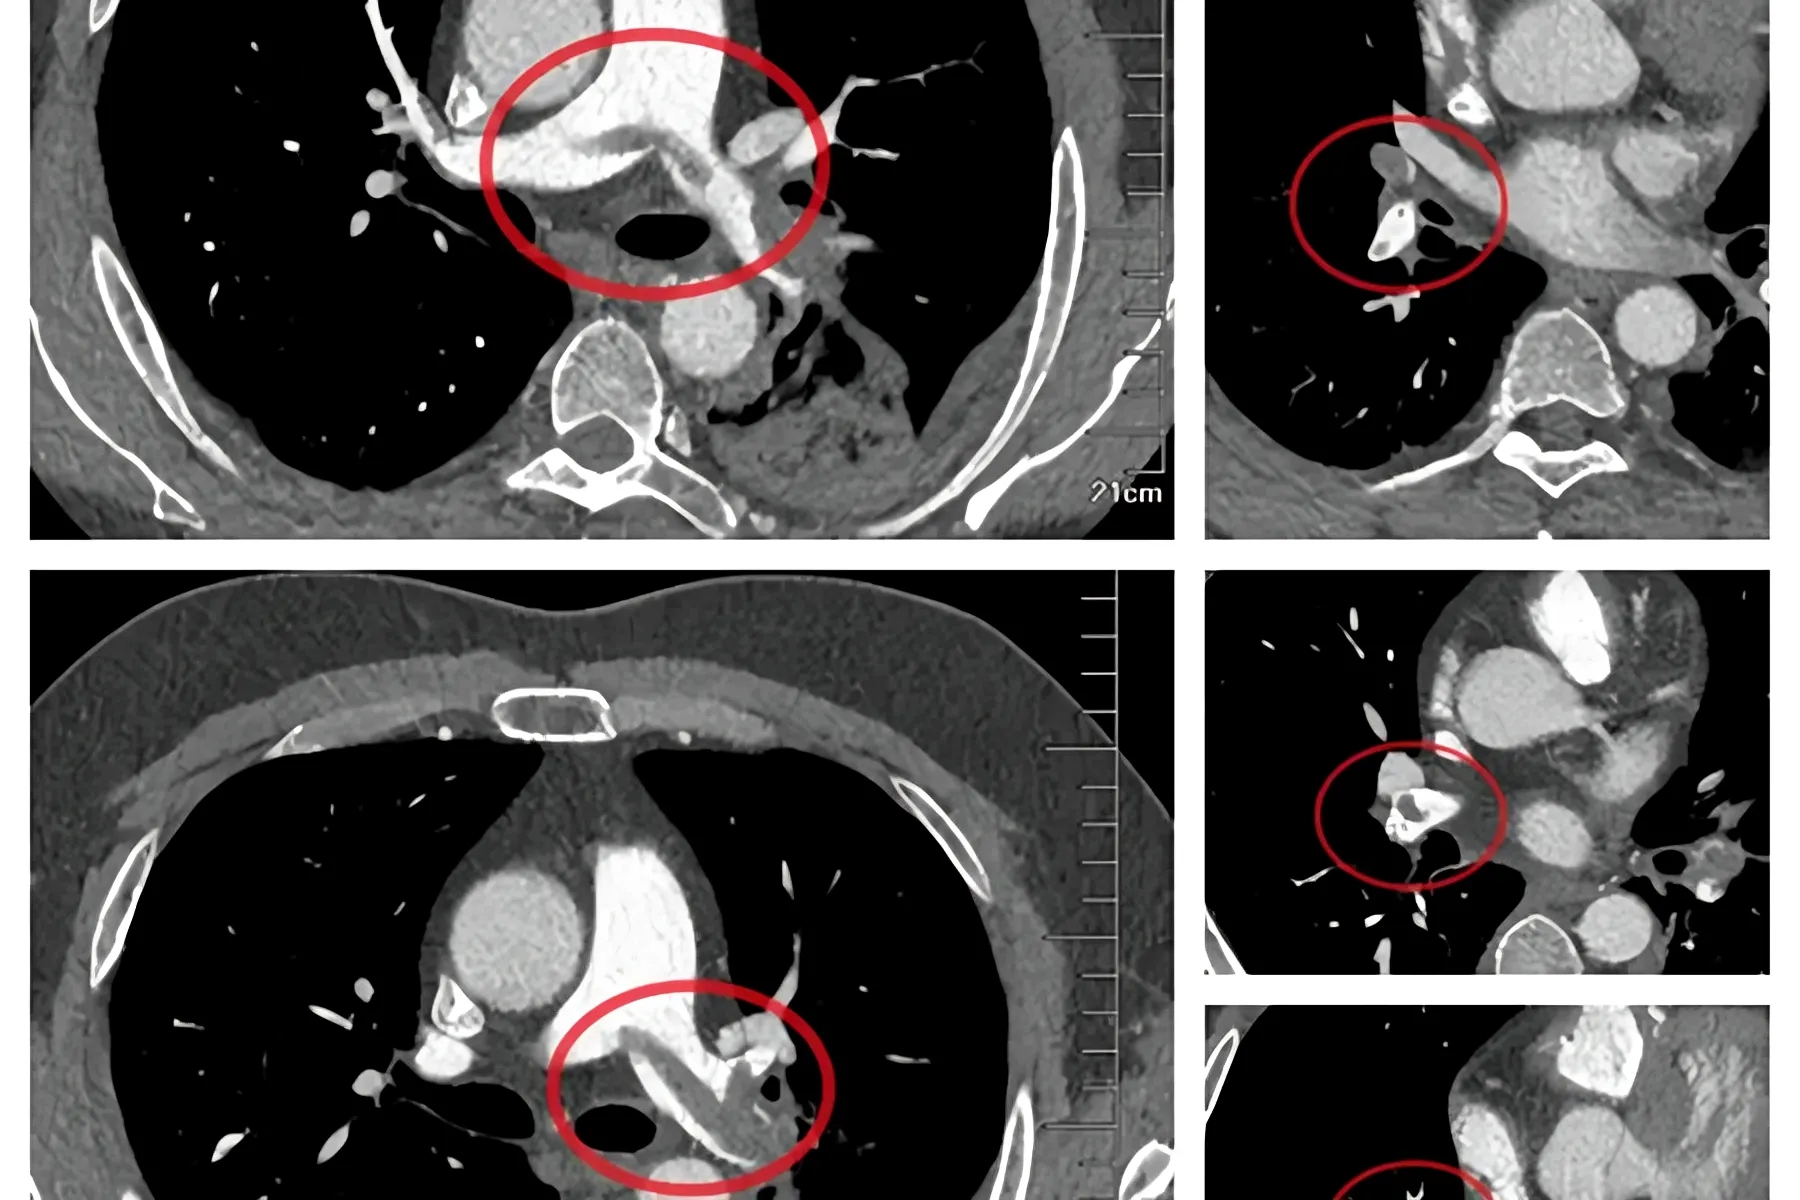

跨越山海的生命之约!3名西藏日喀则先心病患儿来青接受公益救治

近日,在“山海相连·医路同行——雪域童康 桑珠孜区先心病患儿赴青救治项目”的助力下,3名患有先天性心脏病的藏族儿童,带着对远方的懵懂和对健康的憧憬,踏上了人生中第一次青岛之旅,这不...